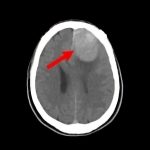

断層撮影

手術前2